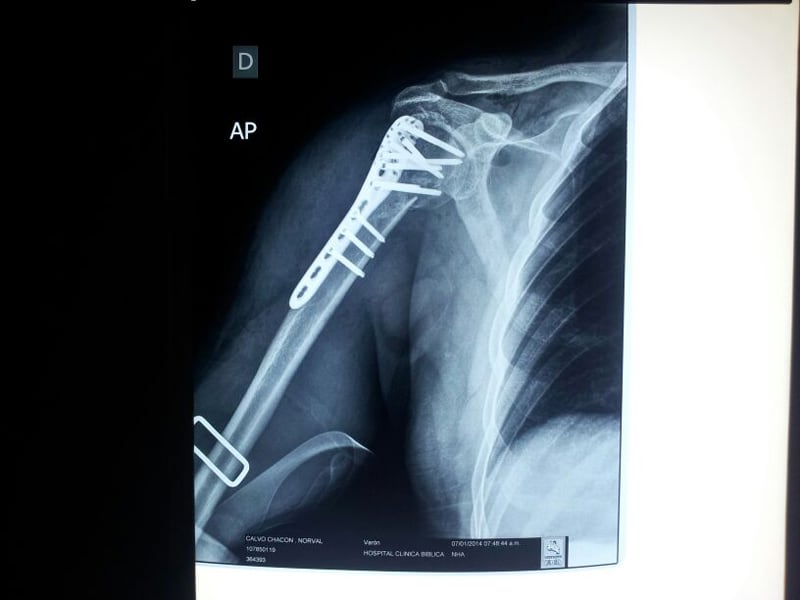

“La operación fue un poco complicada porque duró casi 4 horas. Estuve con anestesia total. Tenía el húmero (hueso que forma parte del hombro) en tres pedazos. Armaron como un rompecabezas y me pusieron una platina con 11 tornillos que lo sujetan”, describió Calvo .

“Me operó también parte del músculo bícep, lo cortó para acomodar todo. Por tener platina no se necesita yeso, debo estar inmovilizado un mes para luego comenzar la rehabilitación”, contó Calvo, quien fue operado por el doctor Fernando Contreras Soares.

“La lesión se localiza en el húmero proximal derecho (parte superior que es uno de los tres huesos del hombro). La cirugía tuvo una duración de 3 horas y media, fue larga y compleja, pero obteniendo un resultado exitoso. Por suerte solo hubo necesidad de ponerle una platina para estabilizar el hueso, y no ameritó de otros procedimientos”, señaló el médico.